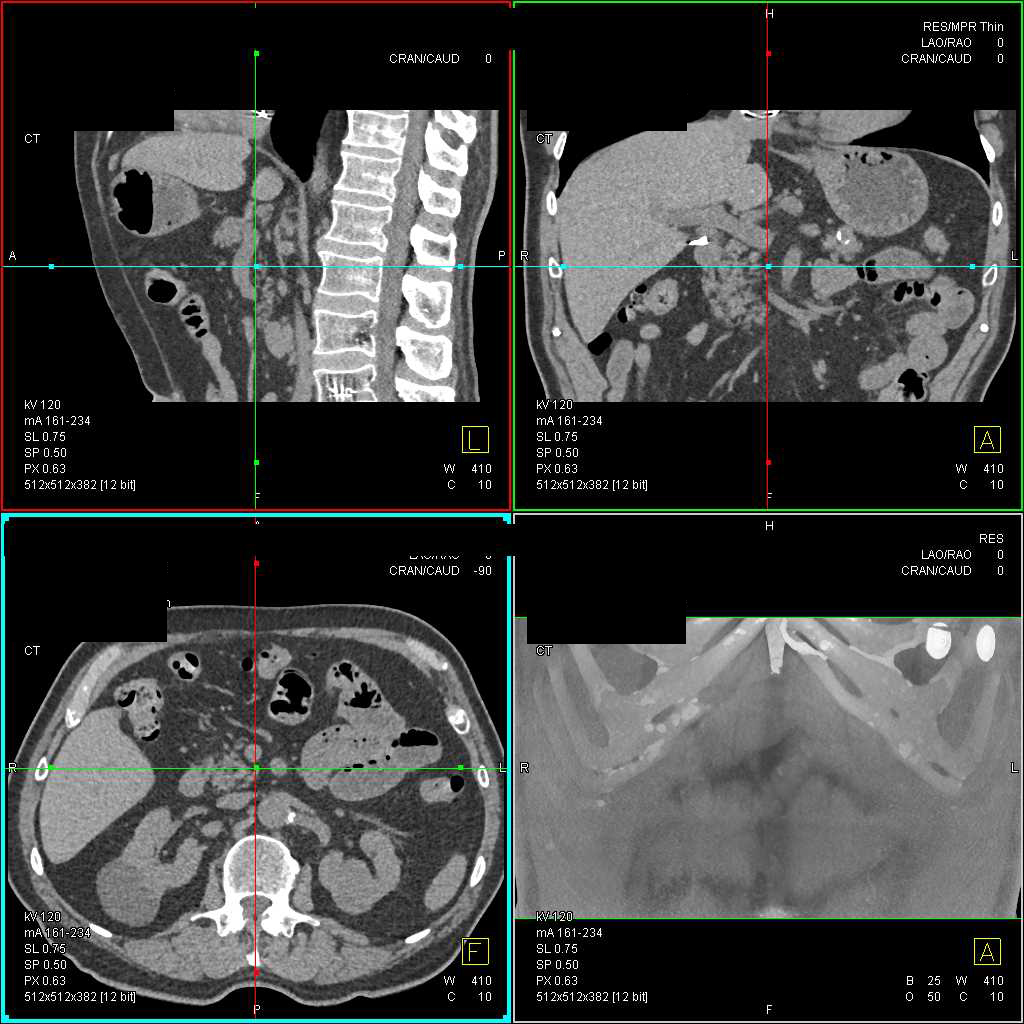

Transitional Cell Cancer (TCC) Right Renal Pelvis, Ureter and Bladder